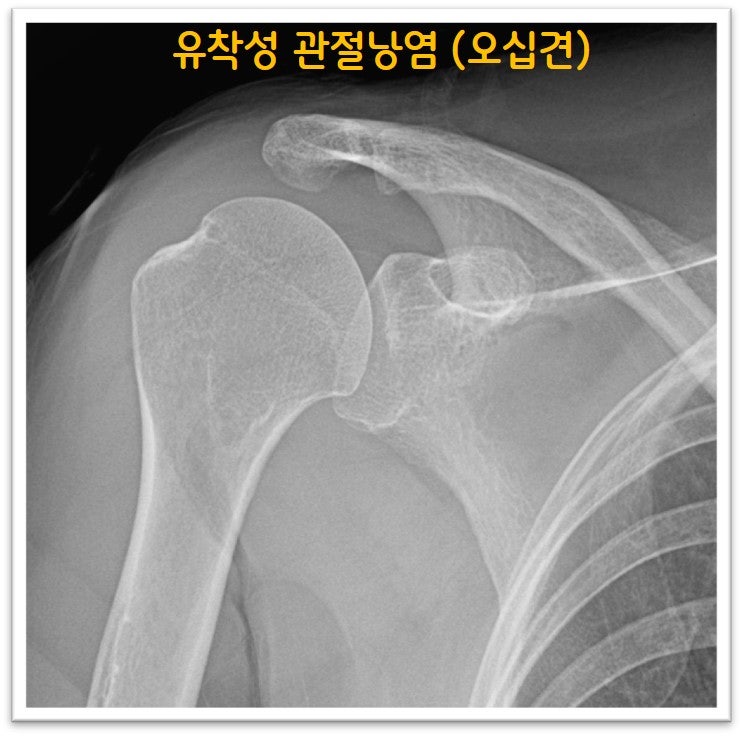

오십견은 의학적 명칭으로 유착성 관절낭염이라 합니다. 즉 관절낭에 염증이 생기면서 유착이 발생되어 통증이 생기고 가동범위 제한이 생기는 것입니다. 치료를 제대로 하지 않을 경우 가동범위 제한이 풀리지 않으며 통증이 지속되고 일상생활에 지장이 있을 만큼 증상을 유발하게 됩니다. 물론 처음부터 시술을 하지는 않으나 적절한 주사치료 및 재활을 했음에도 증상 호전이 되지 않을 때는 뉴핌스 치료 (관절낭유착박리술) 를 통해 탁월한 효과를 볼 수 있습니다. 오십견으로 오랜 기간 동안 고통을 받으시는 분들에게 탁월한 효과와 병의 치료를 할 수 있습니다.